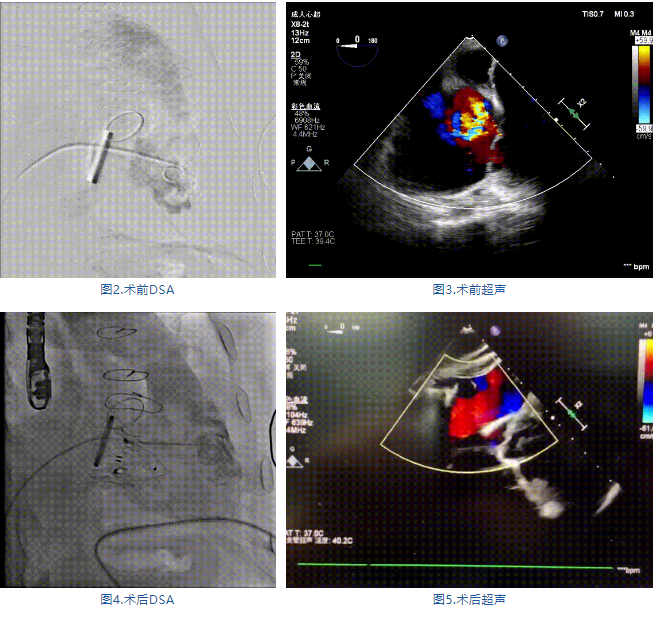

近日,廣東省人民醫(yī)院郭惠明、劉健、謝年謹教授團隊成功應(yīng)用LuX-Valve Plus經(jīng)血管三尖瓣置換系統(tǒng)治療1例左心機械瓣置換術(shù)后重度三尖瓣反流(TR)的患者,手術(shù)獲得圓滿成功!術(shù)后超聲提示LuX-Valve Plus人工三尖瓣瓣膜同軸性良好,無反流和瓣周漏。至此,LuX-Valve Plus全國多中心FIM研究已順利完成全部入組。LuX-Valve Plus全國多中心FIM研究于2022年5月25日開始首例入組,期間克服了全國疫情的重重阻力,短短兩個半月便完成了全部15例患者的入組,為即將開展的確證性臨床研究打下了夯實的基礎(chǔ)。

接受本次治療的是一例三尖瓣重度反流的患者,NYHA心功能Ⅲ級。主訴“反復(fù)活動后氣促1年,下肢水腫4個月”。入院N末端B型腦鈉肽前體(NT-proBNP)3161pg/ml。心電圖提示:心房顫動,ST-T改變。術(shù)前超聲提示:重度三尖瓣關(guān)閉不全,右心房擴大,三尖瓣收縮期位移(TAPSE)14mm,左房增大,左室收縮功能正常低值,主動脈瓣、二尖瓣機械瓣功能良好。術(shù)前CT評估(圖1):三尖瓣瓣環(huán)(周長換算直徑)大小為46.2mm;入路血管無嚴重迂曲,無鈣化;雙側(cè)冠脈有鈣化。

手術(shù)在全麻狀態(tài)下進行,郭惠明教授團隊采用經(jīng)右側(cè)頸靜脈入路的方式送入輸送器進入體內(nèi),并在TEE和DSA的指引下進行。在輸送器進入右室后釋放室間隔錨定裝置,旋轉(zhuǎn)輸送器,使得錨定裝置對準室間隔面;而后釋放前瓣夾持件,確定夾持件位于右室側(cè)釋放LuX-Valve Plus人工瓣膜盤片,再使用DSA和超聲確認盤片是否位于右房側(cè),同時調(diào)整瓣膜的同軸性。緊接著在DSA和超聲的監(jiān)視下調(diào)整室間隔錨定件貼合室間隔,釋放室間隔錨定裝置。再次確認瓣膜的穩(wěn)定性和同軸性后,將輸送器撤出體內(nèi),最終完成LuX-Valve Plus人工瓣膜植入(圖2-5),手術(shù)獲得圓滿成功?;颊咴谑中g(shù)室即刻拔除氣管插管,術(shù)后超聲提示LuX-Valve Plus人工三尖瓣瓣膜同軸性良好,瓣架固定牢靠,無反流和瓣周漏。